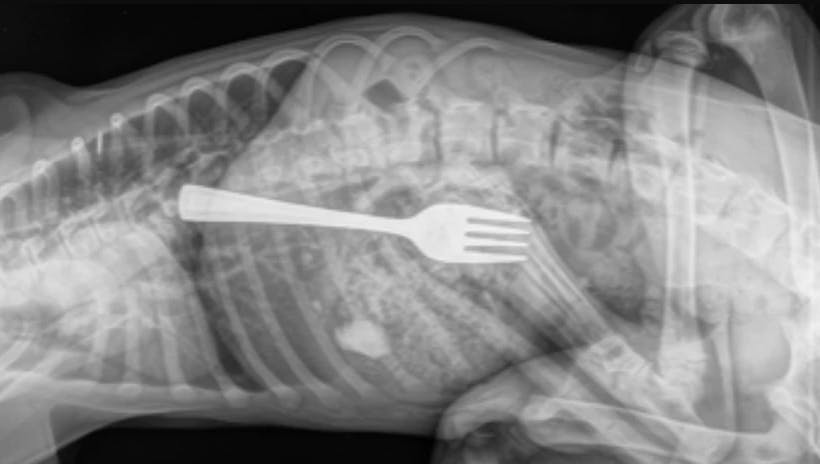

Og rigtig nok: Røntgenbillede viste, at Dustin havde slugt en gaffel, der nu sad godt og grundig fast i dens spiserør.

Gaflen var ikke til at overse. Foto: Michael og Elise Pitt

Derfor frygtede parret, at deres hundehvalp også havde slugt gaflen – og de hastede ham derfor til dyrlægen, der kunne konstatere, at deres frygt var god nok: I Dustins spiserør sad den 10 centimeter lange gaffel.